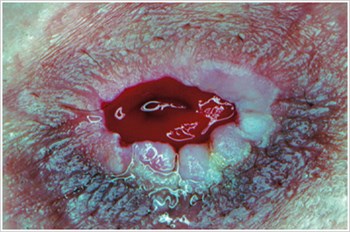

Pioderma gangrenoso

Descrição/Causas:

Uma doença inflamatória da pele frequentemente observada em pacientes com doença inflamatória intestinal (DII), como doença de Crohn ou colite ulcerosa.

Sintomas:

- Úlceras de forma irregular, vermelhas, dolorosas, infetadas, com margens enroladas de vermelho a roxo; aparecem nas pernas, nádegas, rosto e área peristoma.